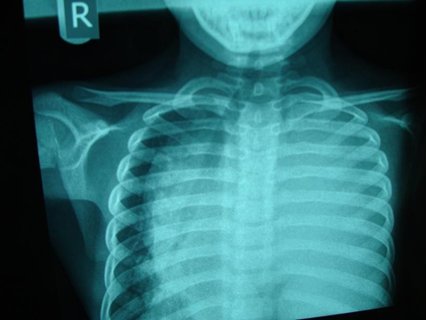

Chest x-ray is not usually diagnostic but may show bilateral diffuse parenchymal infiltrates with a “ground-glass” or reticulogranular appearance, but can be normal or have only mild parenchymal infiltrates. The earliest infiltrates are perihilar, progressing peripherally before reaching the apical portions of the lung.

Chest X-ray (CXR): TB enlarged perihilar lymph nodes are better visualised on a lateral CXR than a PA view, therefore, it is important to obtain both PA and lateral films when evaluating a child with suspected TB.